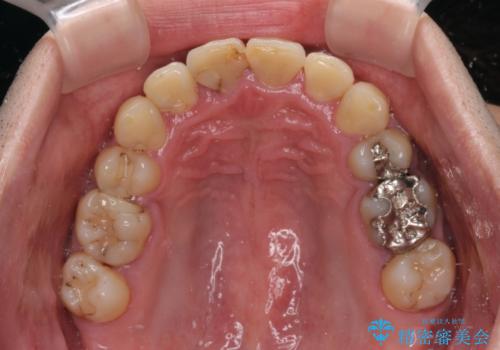

第二小臼歯抜歯の矯正治療は、治療期間が長引くことが多いですが、動きが非常に良く、予定の治療期間で終えることができました。

上下の正中も思っていた以上に良い位置に改善されました。